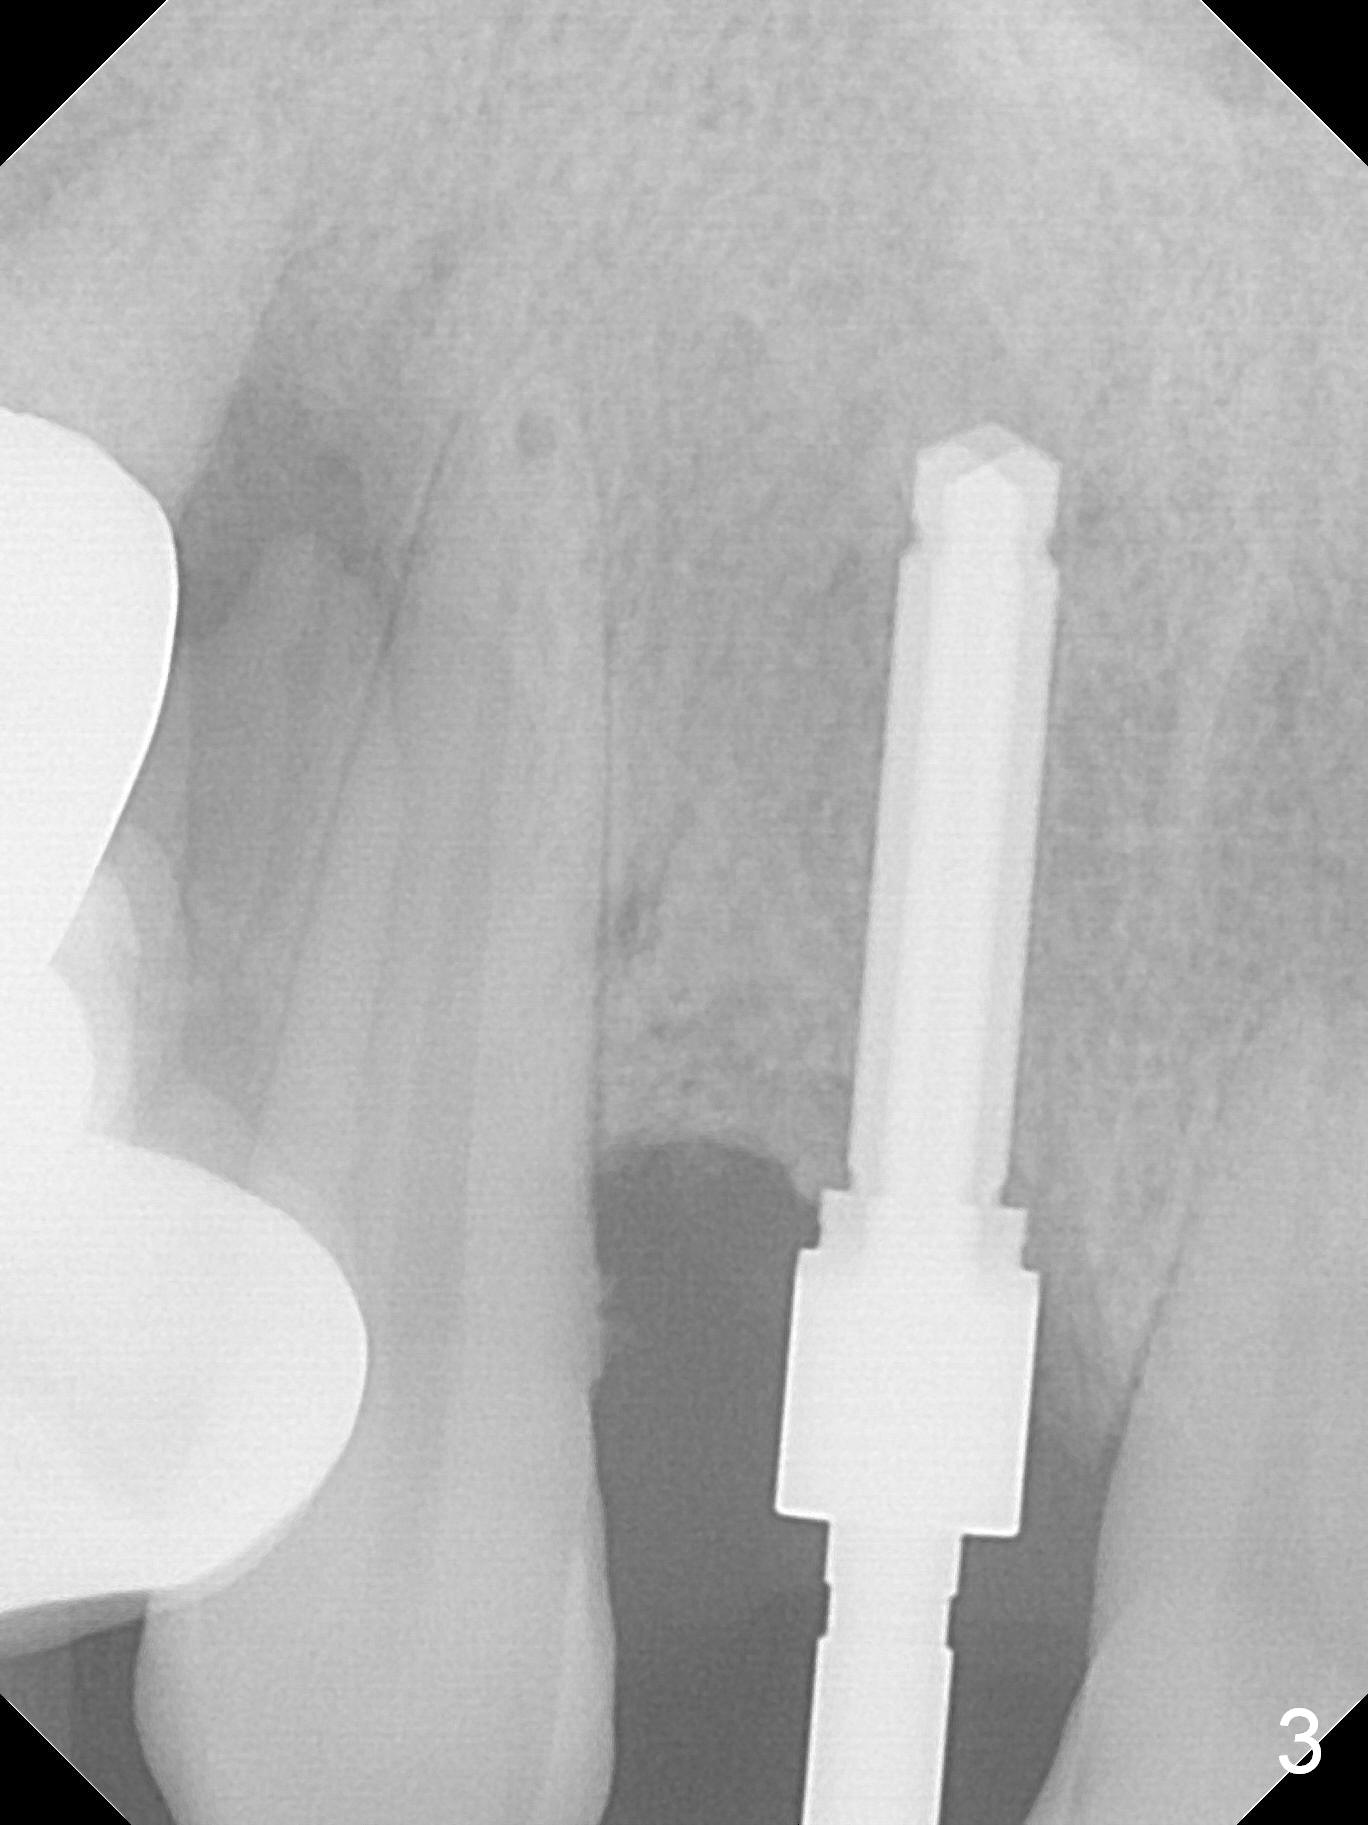

Because of back pain, the 45-year-old man requests less implants (#7 and 13) in the second surgery than the previous one (#9-11, 15).

After extraction of the labioincisally displaced #7 (Fig.1, Metronidazole), place either 1 or 2- (Fig.2) piece implant.  For the latter (bone density 200-800 units), prepare cemented or angled abutments with 5 mm cuff.  Use a crown form for provisional (single unit).